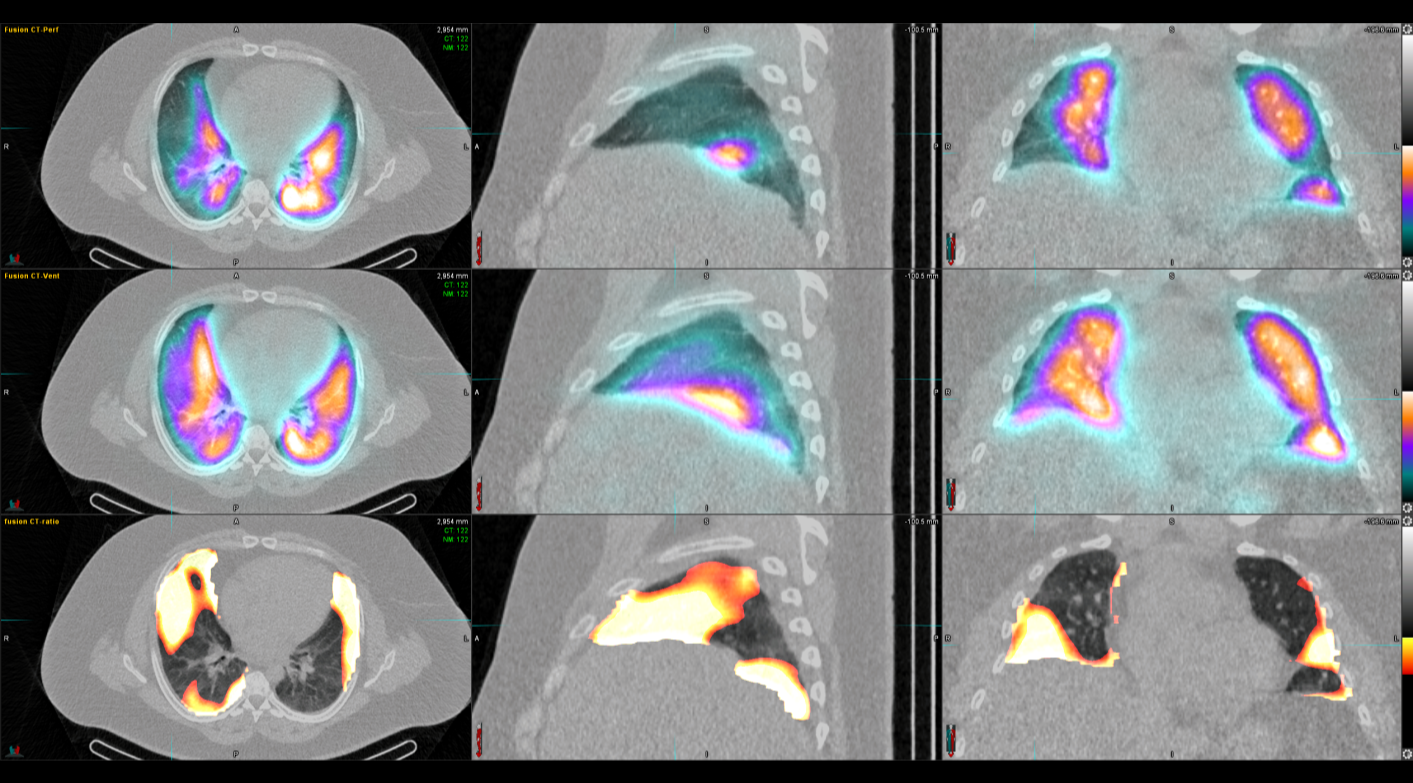

Η θεραπεία με Ύτριο-90 SIR-Spheres (Y-90) αποτελεί μια εξειδικευμένη τεχνική εκλεκτικού ενδοαρτηριακού εμβολισμού, η οποία στοχεύει αποκλειστικά τον όγκο μέσω των ηπατικών αγγείων, επιτρέποντας την εναπόθεση σωματιδίων που εκπέμπουν ραδιενέργεια τοπικά με ελάχιστη ακτινική επιβάρυνση στους υγιείς ιστούς. Η διαδικασία περιλαμβάνει λεπτομερή προθεραπευτικό αγγειογραφικό σχεδιασμό με αξιολόγηση της αγγειακής ανατομίας και χορήγηση ενός ιχνηθέτη για την ανίχνευση τυχόν διαφυγής (πχ. lung shunt), εξασφαλίζοντας μέγιστη ασφάλεια και εξατομίκευση. Η επιλογή της δόσης γίνεται πλέον με σύγχρονα υπολογιστικά μοντέλα δοσιμετρίας και εξειδικευμένα λογισμικά (όπως MIM ή SIR-TeX platform), τα οποία επιτρέπουν ακριβή αποτύπωση του όγκου της νόσου στο ήπαρ, υπολογισμό του πραγματικού tumor burden και εκτίμηση της απορροφούμενης δόσης τόσο στον όγκο όσο και στο υγιές ηπατικό παρέγχυμα. Μετά τη θεραπεία, πραγματοποιείται έλεγχος κατανομής της ακτινοβολίας (μέσω Bremsstrahlung SPECT/CT ή PET/CT), ενώ ακολουθεί στενή απεικονιστική και κλινική παρακολούθηση για την αξιολόγηση της ανταπόκρισης, την εκτίμηση τυχόν τοξικοτήτων και τον σχεδιασμό επόμενων βημάτων στην ογκολογική στρατηγική του ασθενούς. Πρόκειται για μια ιδιαίτερα αποτελεσματική θεραπευτική επιλογή σε πρωτοπαθείς ηπατικούς όγκους και σε ηπατικές μεταστάσεις, ειδικά όταν οι συμβατικές θεραπείες έχουν περιορισμένη αποτελεσματικότητα ή δεν είναι πλέον εφικτές.